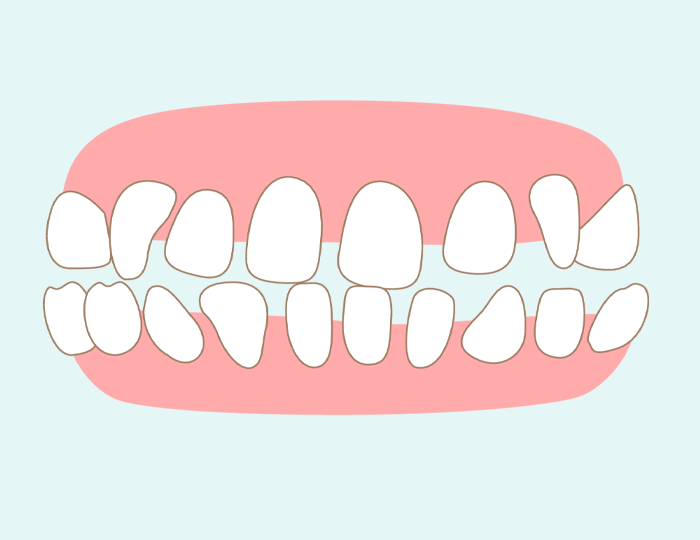

上下顎前突

上下顎が全体的に前に出ているのが、上下顎前突(じょうげがくぜんとつ)です。歯並び自体は整っているように見えますが、不正咬合があると気付かれない傾向があります。前歯への負担が強いことから、将来的に歯槽膿漏になるリスクが高いです。転倒した際に顔面をぶつけると、前歯が抜けたり、歯槽骨が骨折したり、唇を切るなど外科的な怪我につながります。

上下顎前突には歯だけが前に出ているケースと、顎の骨に問題があるケースがあります。骨が原因である場合は、矯正歯科クリニックでの対応が必要となるため、当院からご紹介をさせていただいております。